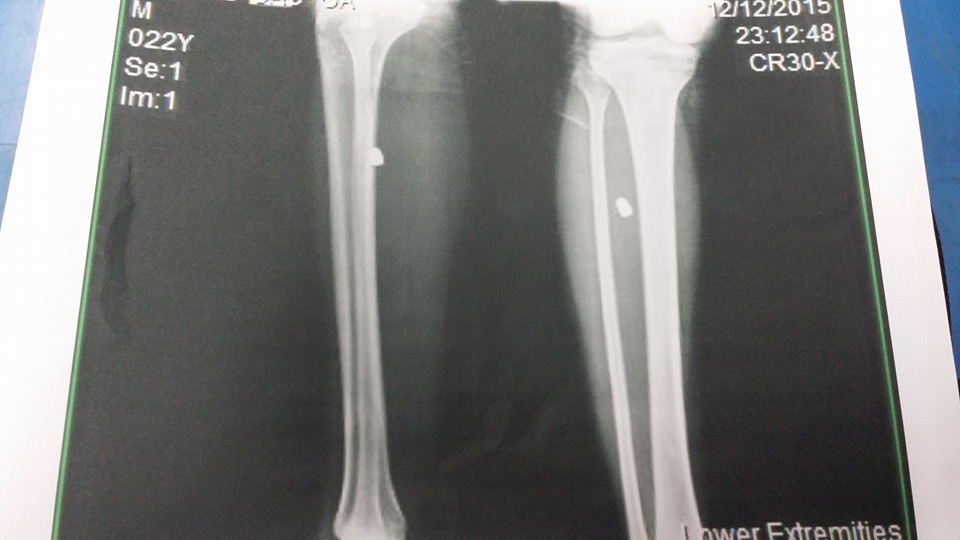

ปัจจุบัน เราหายดีแล้วเดินเริ่มลงน้ำหนักที่เท้าได้แบบปกติแล้วค่ะ แต่กระสุนก็ยังฝังใน (หมอบอกว่าไม่ต้องผ่าออกก็ได้ ????) เชื่อหมอค่ะ T้-T้ หมอบอกว่าเหมือนพกของขลัง